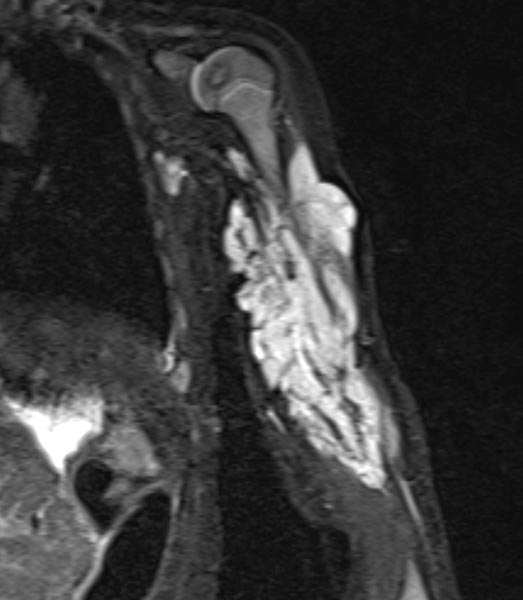

To further confirm the differential diagnosis, the child also underwent MRI, shown here in a coronal, T2-weighted, fat-suppressed STIR sequence. The tumor is highly hyperintense (white) and sharply demarcated from surrounding tissue. It penetrates all tissue planes and centrally contains signal-free areas, so-called flow voids, as a sign of strong arterial perfusion.